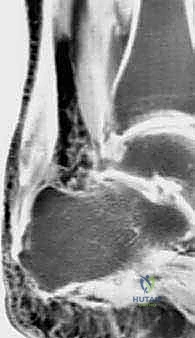

وتر أخيل ليس مجرد وتر عادي؛ إنه الكابل الحيوي الأقوى والأضخم في جسم الإنسان. يربط هذا الوتر الجبار عضلات الساق الخلفية (عضلة السمانة) بعظم الكعب، وهو المحرك الأساسي الذي يسمح لك بالوقوف على أطراف أصابعك، والمشي، والجري، والقفز. ولكن، عندما يتعرض هذا الوتر لإجهاد متكرر على مر السنين، أو نتيجة لعوامل بيولوجية وميكانيكية معينة، فإنه يبدأ في التآكل. تتدهور أليافه الكولاجينية القوية، وتتحول إلى نسيج ندبي ضعيف ومؤلم، وتزداد سماكته بشكل مرضي، مما يجعله ليس فقط مصدر ألم دائم، بل يجعله قنبلة موقوتة معرضة للتمزق الكامل في أي لحظة.

لفهم عبقرية هذه الجراحة، يجب أن نفهم التشريح. وتر العضلة المثنية الطويلة لإبهام القدم (Flexor Hallucis Longus - FHL) هو وتر يمر في الجزء الخلفي من الساق، قريباً جداً من وتر أخيل، ويمتد نزولاً ليتحكم في حركة انثناء إصبع القدم الكبير.

5. نقل وتثبيت الوتر (Tenodesis & Fixation)

هنا يتجلى الفن الجراحي. يتم حفر نفق صغير جداً في عظم الكعب (Calcaneus). يُسحب وتر FHL القوي ويُزرع داخل هذا النفق العظمي. يتم تثبيته باستخدام مسمار تداخلي حيوي (Bio-interference screw) يندمج مع العظم بمرور الوقت، مما يوفر تثبيتاً صخرياً قوياً.